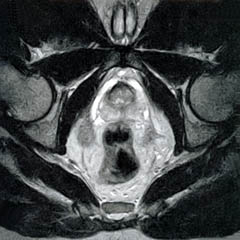

The Prostate without an Endorectal Probe |

The Heart |

![]() |

| Prostate: Delineation of Peripheral Zones (PZ), Cortical Zone (CZ) and Vescicles without an Endorectal Coil. | |

|

Bladder

and Uterus in Pelvic Floor Dysfunction (PFD) |

Figure 8.

Figure 8a-8d.

Further examples of the exceptional anatomic detail

made visible by the DISCOVERY

of Damadian of the pronounced differences in the decay

rates (relaxations) of the NMR signals

of the body's normal tissues (Figure

6). The DISCOVERED

differences supply the pixel amplitude differences

"PIXEL CONTRAST (IMAGE DETAIL)"

that produce, for the first time in medical history,

the detailed visualization of normal human anatomy

MRI is noted for. Note the visualization of the